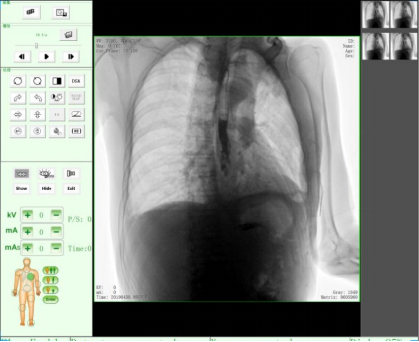

動態(tài)DR17*17英寸非晶硅動態(tài)平板探測器,透視像素達(dá)200萬,可實(shí)時顯示大幅面高清拍攝視野。適用于全身各部位攝影,包括常規(guī)攝影,如胸片、頸椎、腰椎、腹部、頭顱、四肢等,以及特殊攝影。

適用于全身各部位的透視檢查及輔助治療,如隱匿性肋骨骨折、胸透檢查、骨折復(fù)位、小兒腸套疊空氣灌腸等。同時具備多種幀率透視模式,影像更加流暢、準(zhǔn)確。